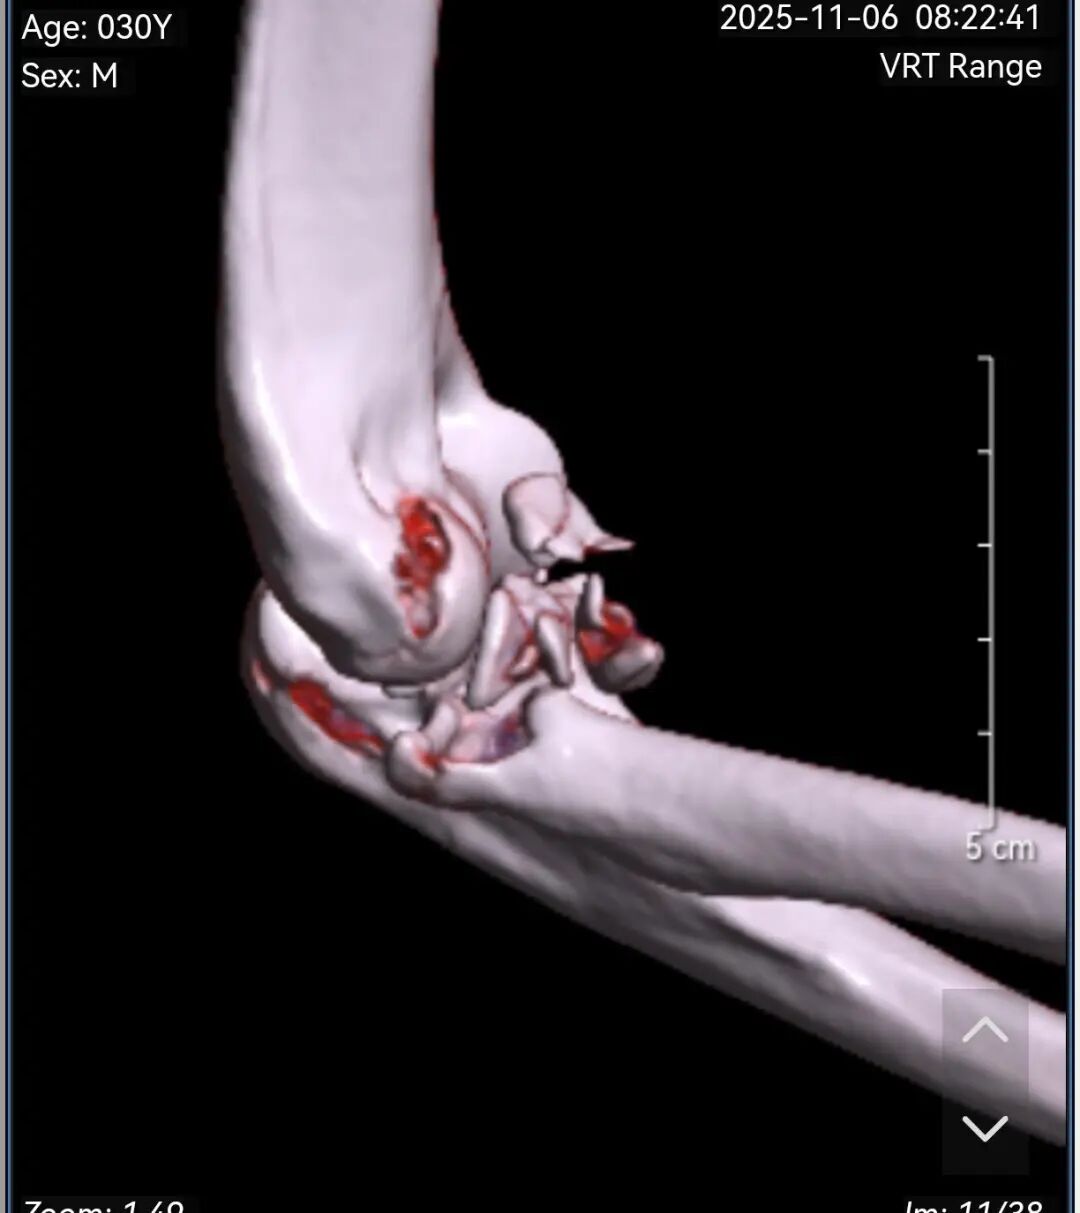

黄益平主任接诊后,经详细询问病史、查体并完善相关检查后,明确诊断为 “右肘关节恐怖三联征( 右尺骨冠突骨折、右桡骨小头粉碎性骨折 、肘关节后脱位已复位)”。

患者术前影像

恐怖三联征

“恐怖三联征, 是肘部最复杂的高能量创伤之一 ”,黄益平主任介绍,该病症因涉及骨性结构与软组织的复合损伤, 治疗难度极大, 若处理不当易导致关节僵硬、不稳定、创伤性关节炎等后遗症,甚至可能造成永久性功能障碍。

黄益平主任随即带领骨科团队进行了全面的评估和讨论,结合患者伤情及影像学检查结果,制定了精准的治疗方案: 右肘关节恐怖三联征骨折切开复位内固定+韧带重建修复肘关节稳定术。